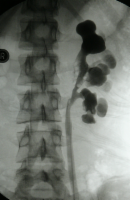

Bei Harnstaus ist eventuell eine retrograde Sondierung mit Sicherung einer Ureterabgangsstenose angezeigt (Abbildung 8) (

s. Bildgebende Verfahren/Retrogrades Pyeologramm).